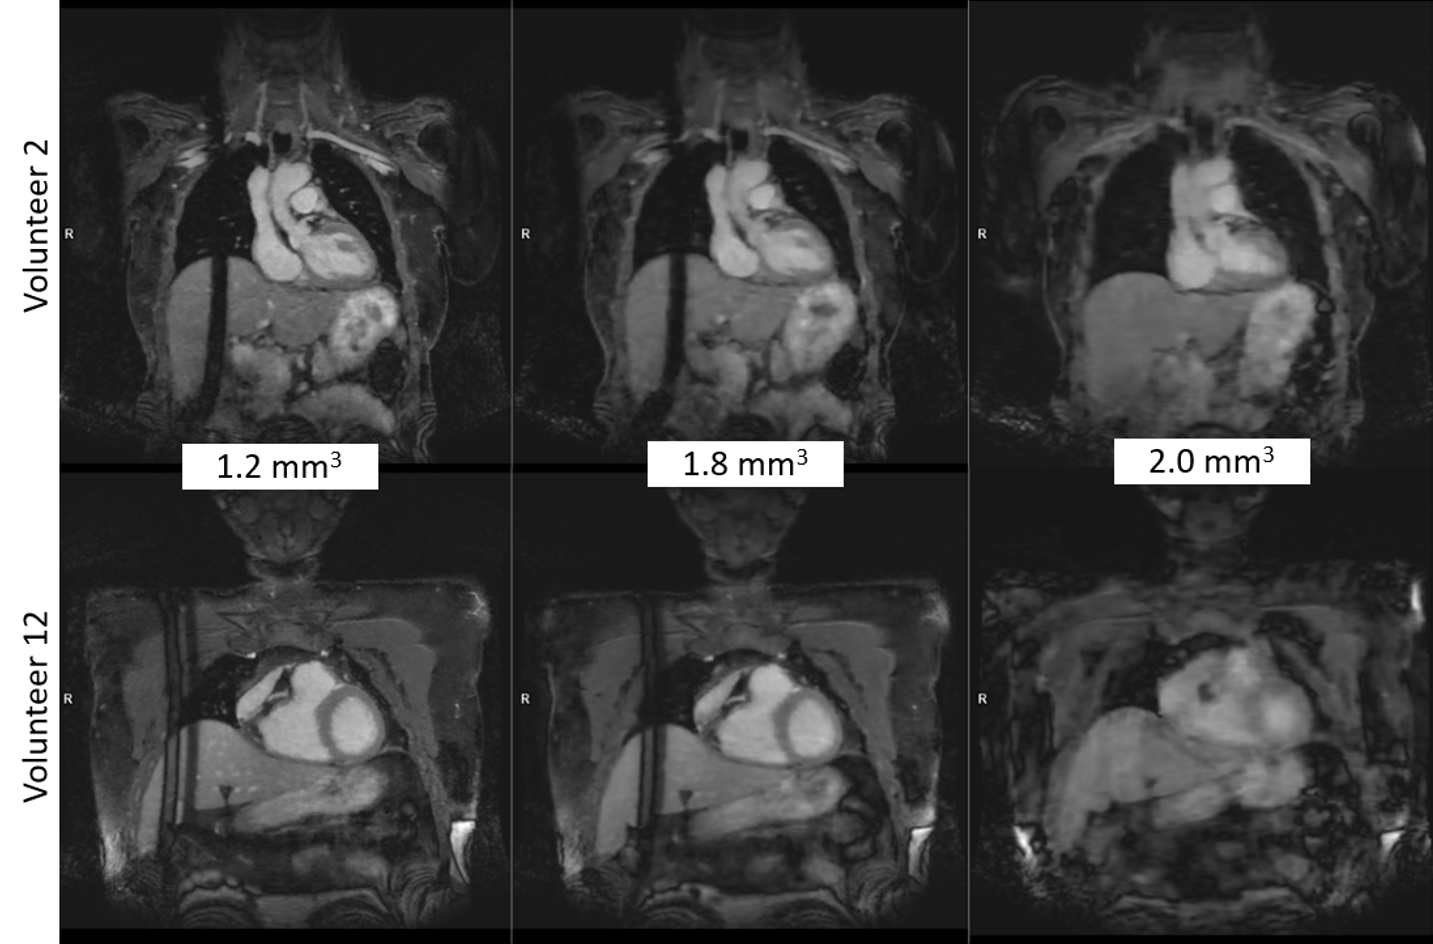

Figure 2: Examples of the 3D MRA image quality of two volunteers for all resolution variants. Volunteer 12 did not hold their breath until the end of the acquisition for the 2 mm^3 breath-hold variant, which resulted in lower image quality.